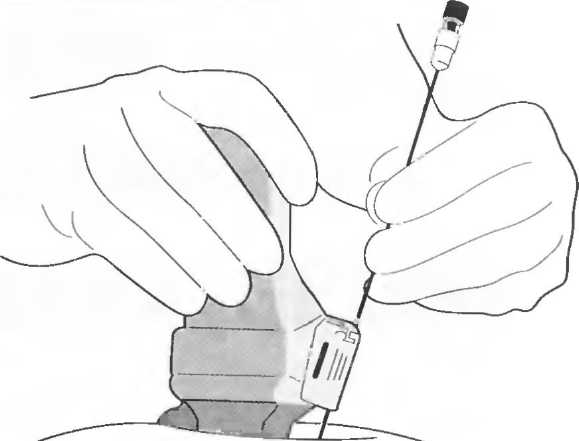

1. Подготовка

Пациент не должен пить и есть в течение 8 ч перед исследованием. Если жидкость необходима для предотвращения дегидратации, можно давать пациенту только воду. При острой симптоматике исследование можно проводить без подготовки. Детям, если позволяют клинические условия, пища и вода не даются в течение 3 ч до исследования.

При более углубленном исследовании, если нет клинических противопоказаний, может быть полезным дополнительный прием воды, особенно при исследовании поджелудочной железы, нижних отделов живота и таза.

2. Положение пациента. Пациент может лежать в удобной позе на спине. Под голову можно положить маленькую подушку, в случае выраженного напряжения передней брюшной стенки подушечку можно поместить также под колени пациента.

Намажьте живот гелем.

Пациенту разрешается дышать спокойно, однако при исследовании отдельных органов требуется задержка дыхания на вдохе.

3. Выбор датчика. Используйте датчик 3,5 МГц для взрослых и датчик 5 МГц для детей и худых взрослых. Предпочтительны конвексные или секторные датчики.

4. Установите правильный уровень общей чувствительности. Начинайте исследования, поместив датчик центрально в верхней части живота под мечевидным отростком и попросите пациента глубоко вдохнуть и задержать дыхание на вдохе.

Поверните датчик направо до того, как начнет визуализироваться печень. Отрегулируйте чувствительность, чтобы изображение имело нормальную однородную зхоструктуру. Должна быть хорошо различима высокоэхогенная линия диафрагмы сразу за задними отделами печени (рис. 27а).

Воротная и печеночные вены должны визуализироваться как трубчатые структуры с анзхогенным просветом. Стенки воротной вены высокозхогенны, но стенки печеночных вен практически не видны (рис. 276).

Рис.27а. Продольный срез. Неизмененная печень и диафрагма.

Рис.27б. Продольный срез: печеночные и воротная вены.

Рис.27в. Поперечный срез через неизмененную печень.

Техника сканирования

После того как вы отрегулировали чувствительность прибора, медленно передвигайте датчик от средней линии вправо, через каждый сантиметр останавливаясь и проверяя изображение. Проверяйте на различных уровнях. После того как вы исследовали правую сторону, таким же образом исследуйте и левую сторону. При этом датчик нужно направлять в различных направлениях, для того чтобы лучше локализовать объект и получить больше информации. Очень важно исследовать всю брюшную полость: если после изменения угла наклона датчика верхняя часть печени или селезенки не визуализируются, необходимо проводить сканирование через межреберные промежутки.

После этих поперечных сканов разверните датчик на 90° и снова начните сканировать от мечевидного отростка. Снова локализуйте печень и при необходимости попросите пациента задержать дыхание на глубоком вдохе, чтобы визуализировать ее лучше. Убедитесь, что уровень чувствительности установлен правильно. При необходимости наклоняйте датчик по направлению к голове пациента. Проводите исследование по межреберным промежуткам.

Ниже ребер держите датчик в вертикальном положении и передвигайте его по направлению к ногам (каудально). Повторите в различных вертикальных плоскостях по всему животу.

Если какая-нибудь часть живота визуализируется плохо, можно проводить исследование в положении больного сидя или стоя. При необходимости проводится исследование в положении пациента на боку с приподнятой головой; чаще зто используется при исследовании почек и селезенки. Не стесняйтесь поворачивать пациента. Если вы заподозрили патологию, используйте технические приемы, описанные в соответствующих разделах.

Важно визуализировать:

|

1. |